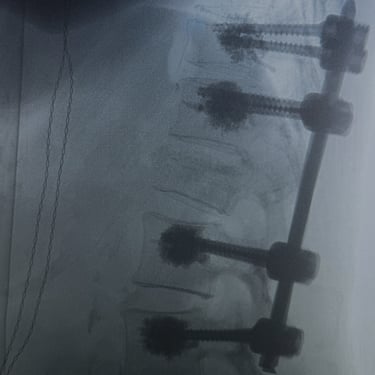

🧠 Artrodesis Lumbar Percutánea | Fijación mínimamente invasiva.

La artrodesis lumbar percutánea estabiliza la columna mediante tornillos y barras colocados por pequeñas incisiones, con mínima agresión muscular. Indicada en inestabilidad, fracturas o listesis, ofrece menor dolor postoperatorio, menor sangrado y recuperación más rápida. Es una técnica eficaz y segura para mejorar la función y calidad de vida.